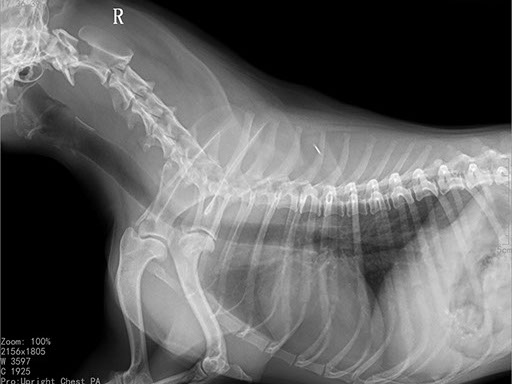

Коллиматорный прицел формирует пучок рентгеновского излучения на участок исследования. Проходя через ткани тела, излучение попадает на плоскопанельный цифровой детектор, который, в свою очередь, передает сигналы на компьютер.

В считанные секунды полученные данные обрабатываются компьютером посредством установленной на него программы визуализации, и сформированное клиническое изображение выводится на монитор лаборанта.

Клинические изображения (снимки) можно напечатать на принтере, сохранить в архиве или отправить по сети коллегам для оперативного консилиума.

Цифровая рентгеновская установка ASR-6150C поставляется с мобильным столом пациента и комплектом рентгенопрозрачных анатомических ложементов всех размеров, видов и пород домашних животных.